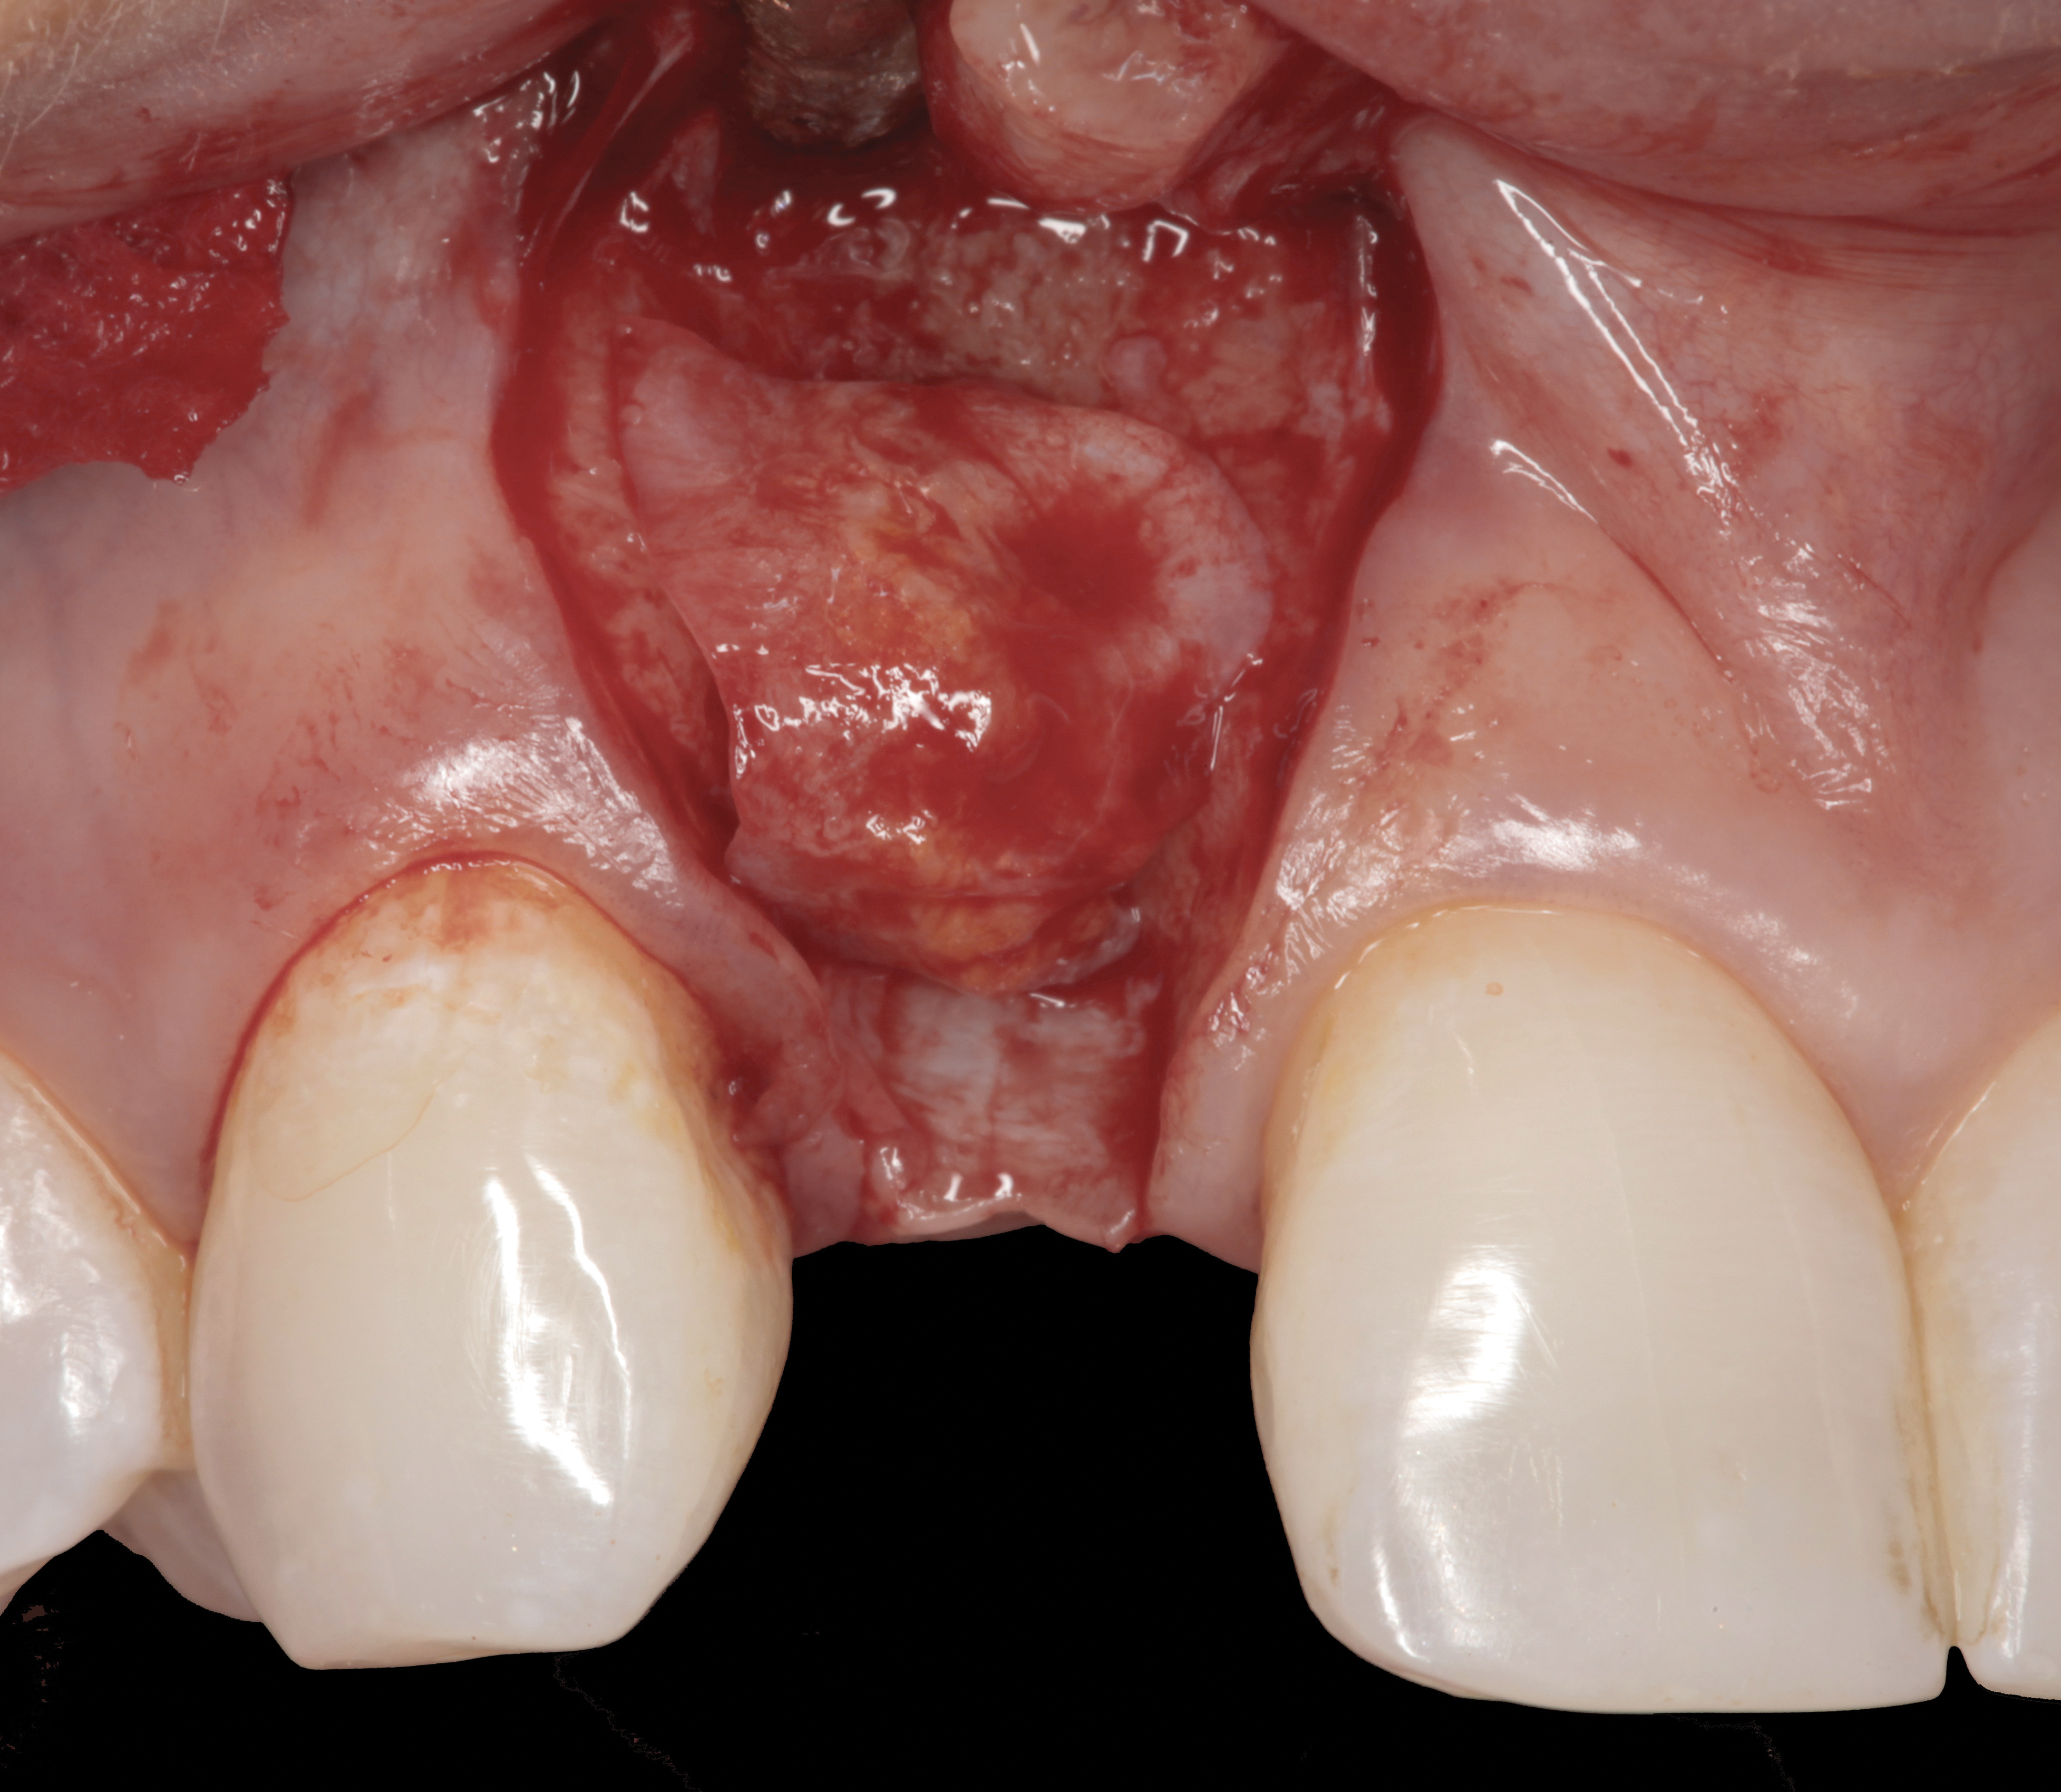

A surgical flap procedure was performed with the intent of thoroughly debriding the granulomatous tissue from the osseous defect (Figure 18 and Figure 19), mechanically and chemically detoxifying the surface of the implant (Figure 20 through Figure 22), and grafting the infrabony component of lesion with bone xenograft (Bio-Oss®, Geistlich Pharma, www.geistlich-na.com) in an attempt to reduce the vertical defect (Figure 23). To concurrently resolve the mucogingival problem, the plan called for placing a dermal allograft (Dermis Allograft, DENTSPLY International, www.dentsply.com) on the buccal (Figure 24) and then replacing the flap (Figure 25).

Fig 18. A full-thickness flap from teeth Nos. 18 to 20 revealed granulomatous tissue in the circumferential defect around implant No. 19.

Figure 18

Fig 19. The circumferential defect was debrided. Note excess cement extending apically from the margin of the crown into the defect; residual cement has been shown to be complicit in the development of peri-implant disease.

Figure 19